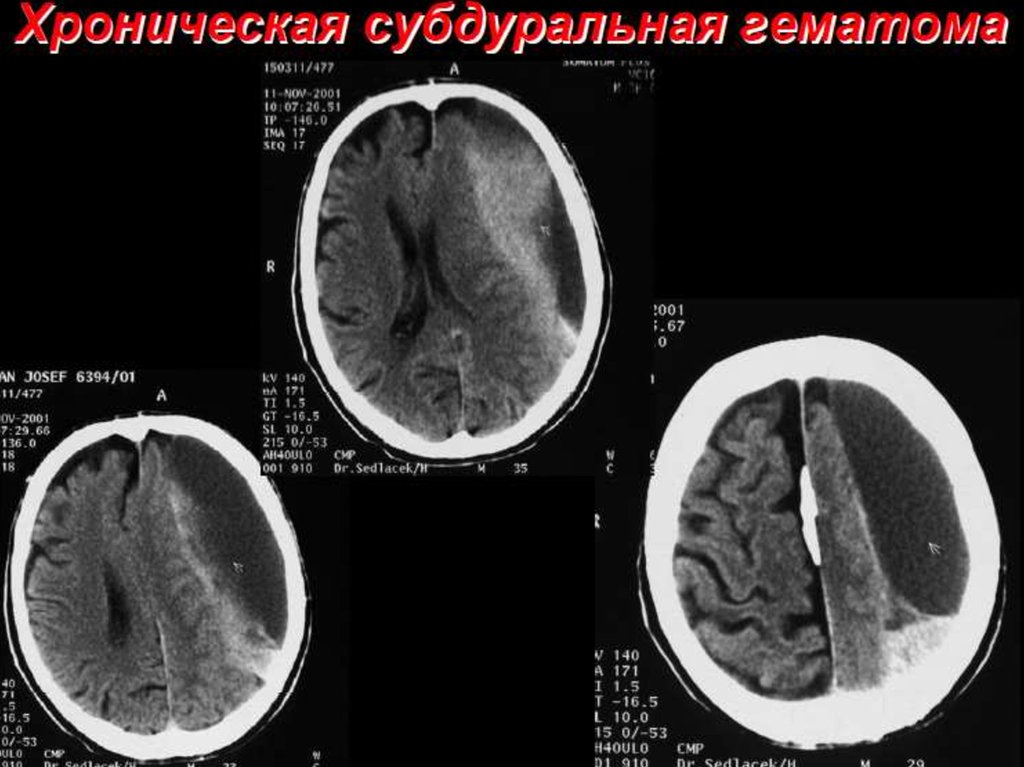

ЧЕРЕПНО-МОЗГОВАЯ ТРАВМА, ПОЗВОНОЧНОСПИННОМОЗГОВАЯ ТРАВМА